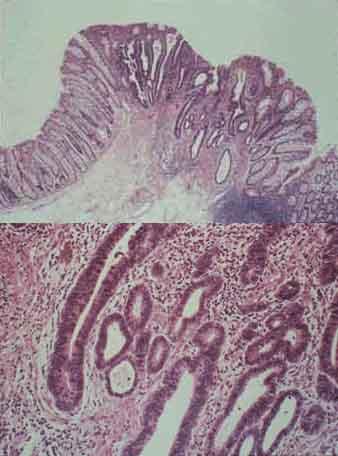

疾患(病理主体)の分類悪性上皮性腫瘍/腺癌

部位(臓器別)大腸/横行

検査方法ミクロ

腫瘍の肉眼分類0型(表在型)/IIc型(IIc)